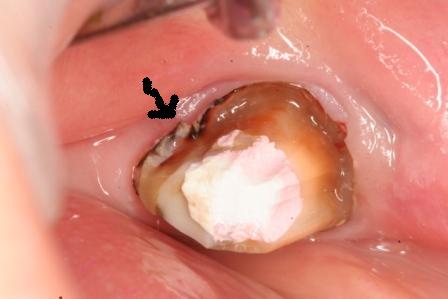

下顎7番の頬側歯茎部カリエスの原因 2025.06.04